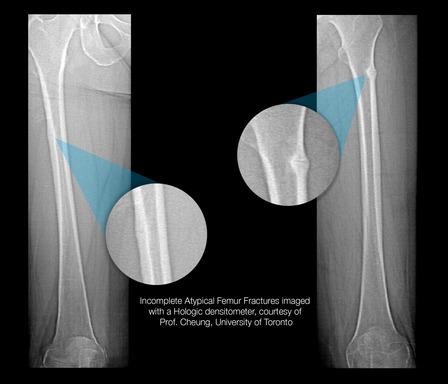

Incomplete Atypical Femur Fractures imaged with a Hologic densitometer, courtesy of Prof. Cheung, University of Toronto.

- A Single-Energy Femur Exam that allows clinicians to visualize potential atypical femur fractures, an unusual form of femur fracture which can occur as the result of bisphosphonate use;